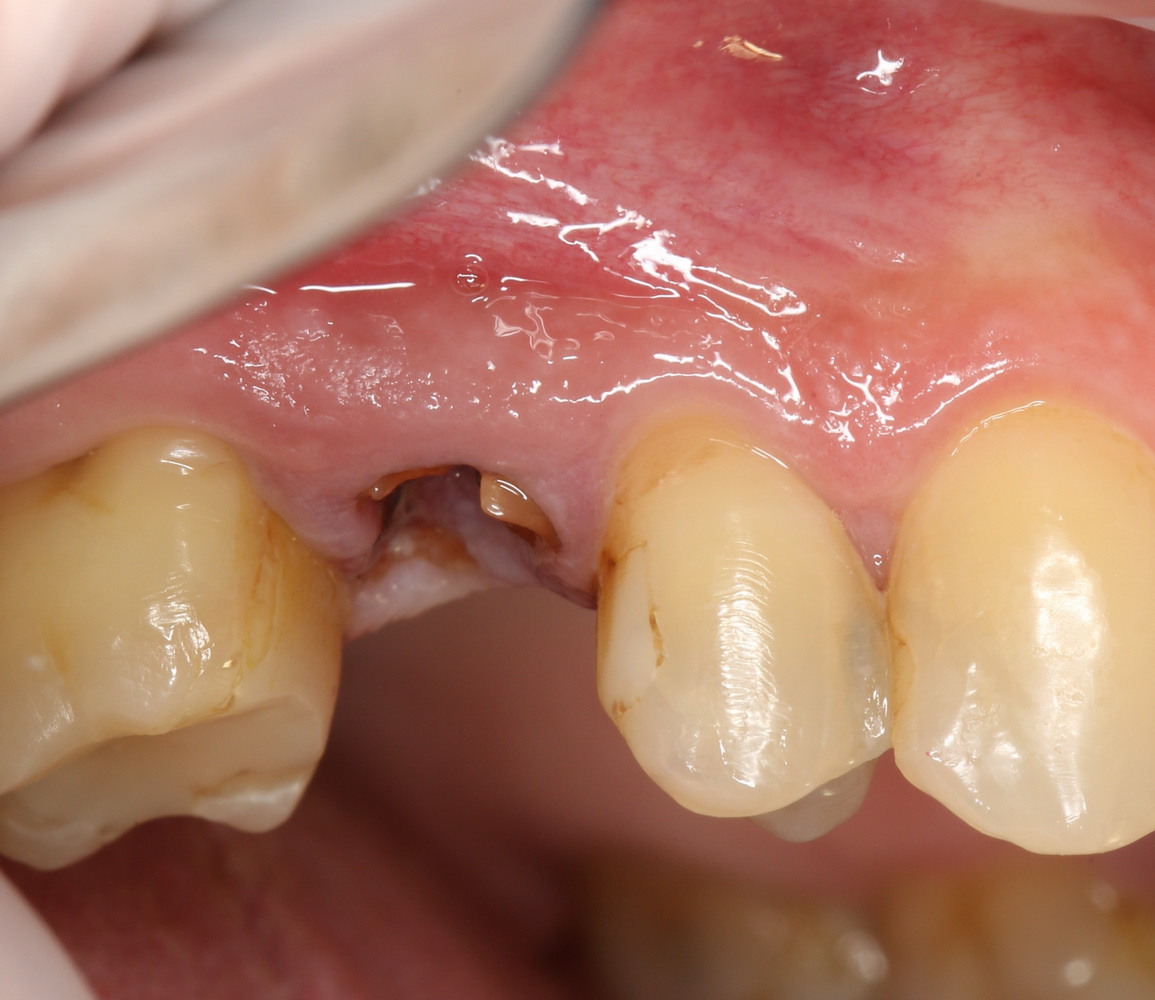

Около трёх лет назад к нам в клинику обратилась пациентка Мария, на момент обращения ей было 45 лет. Её беспокоила ситуация с передними резцами:

В ходе беседы она рассказала, что лечит эти зубы всю сознательную жизнь — их депульпировали («удалили нерв») из-за последствий травмы еще в школьном возрасте, и после этого каждые несколько лет (а то и чаще) ей приходилось перелечивать каналы, менять коронки, вкладки и т. д.

В результате, зубы приобрели очень уж нездоровый вид (см. фото выше). Вдобавок, всё усугубилось существенным снижением качества жизни — коронки и вкладки из зубов постоянно выпадают, десна вокруг них кровоточит при чистке…. Кроме того, Марию не покидает ощущение того, что эти зубы могут просто вывалиться в самый неподходящий момент. Именно это заставило её обратиться в нашу клинику.

Визуальный осмотр:

Подвижность зубов (или коронок) II-III степени косвенно свидетельствует о разрушении периодонтальных связок и стенок лунок зубов. Подвижность является следствием хронического воспаления, когда окружающие зуб ткани остаются без питания и деградируют — и в совокупности это может существенно осложнить сохранение эстетических параметров окружающих имплантат тканей. Степень риска — высокая.

Слизистая оболочка в области центральных резцов отёчна, при прикосновении кровоточит — прямое следствие хронического воспаления. Пока слизистая оболочка воспалена, она не способна к регенерации. Это значит, что операционные раны на такой слизистой вряд ли будут нормально заживать. Степень риска — высокая.

Рецессия десны из-за хронического воспаления — признак запущенного длительного существующего воспалительного процесса, в результате которого разрушается, в том числе, костная ткань. В таких условиях её регенеративная способность, не говоря уже свойствах десны, существенно снижается. Скорее всего, на КЛКТ мы увидим утрату вестибулярной стенки лунки (что объясняет подвижность). Степень риска — высокая.